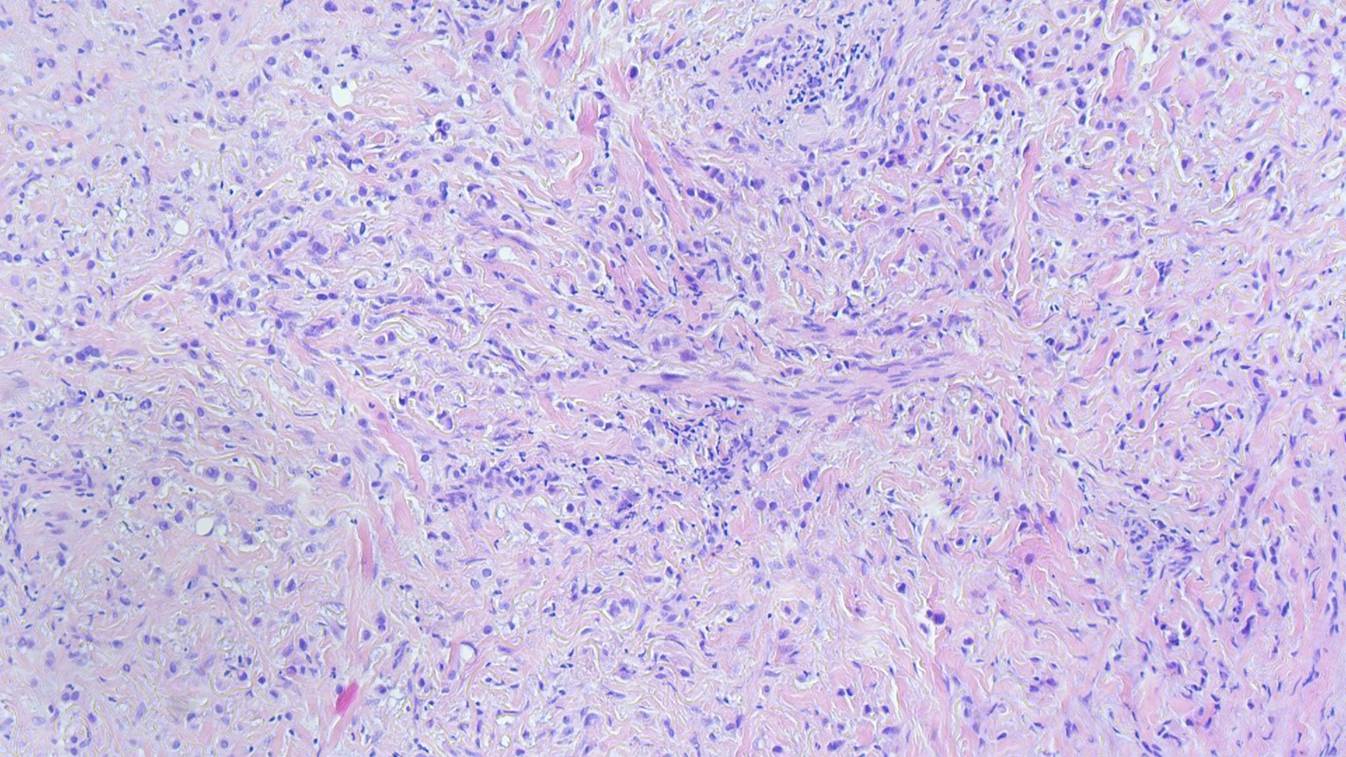

Aufgrund der Akuität der Symptomatik, ungewöhnlichen Lokalisation des Ödems und raschen Progression entschieden wir uns zur Entnahme einer spindelförmigen Hautbiopsie zur weiterführenden Diagnostik. Histologisch zeigten sich im Bereich der Lederhaut diffus einzelzellig und infiltrativ wachsende, plasmazytoide Tumorzellen (Abb. 3). In den immunhistochemischen Zusatzuntersuchen zeigten diese Infiltrate CK20- und CK7-Reaktivität (Abb. 4), eine nukleäre Expression von GATA3 (Abb. 5) und teilweise Positivität gegenüber dem proliferationsassoziierten Antigen Ki67 (Mib1) bei negativer Reaktion gegenüber CK5/6, Östrogenrezeptor, CD68, Androgenrezeptor, CDX2 und NKX3.1.

Abb. 3

Diffus einzelzellig und infiltrativ wachsende, plasmazytoide Tumorzellen innerhalb der Lederhaut. (Hämatoxylin-Eosin-Färbung, Originalvergrößerung 100:1)